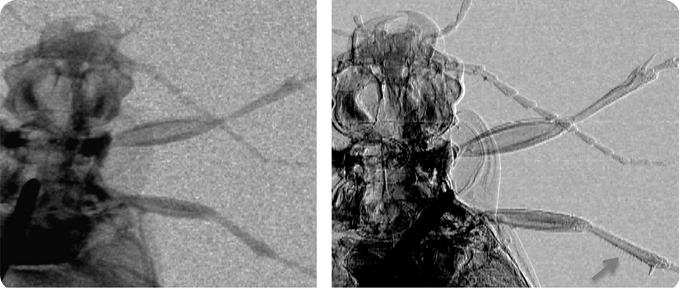

ground beetle x-ray

Attentuation (left) and phase (right) images of a ground beetle. The arrow in the bottom right corner of the latter image shows how thin hairs on the insect’s leg are visualized thanks to phase effects. Credit: Advanced X-Ray Imaging (AXIm) Group, UCL